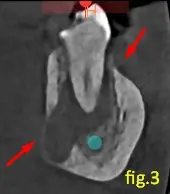

En los cortes axial y transaxial (figuras 2 y 3) se observa que provoca una licuefacción en la medular, abombamiento en la tabla lingual con posterior adelgazamiento, y en algunas zonas se puede observar dificultad para su localización, puede estar relacionada a las caries que presenta en la misma.

Estos signos imagenológicos son compatibles con una osteomielitis crónica.